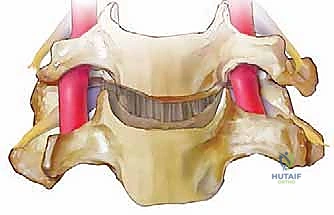

الخطوة 6: زراعة الطعم العظمي (Bone Graft Insertion)

بعد إزالة القرص، تتبقى فجوة بين الفقرتين. لمنع انهيار هذه المسافة ولتحفيز التحام الفقرتين معاً، يتم إدخال "طعم عظمي" أو قفص صناعي (Cage) مصنوع من مادة PEEK أو التيتانيوم ومملوء بمادة عظمية.